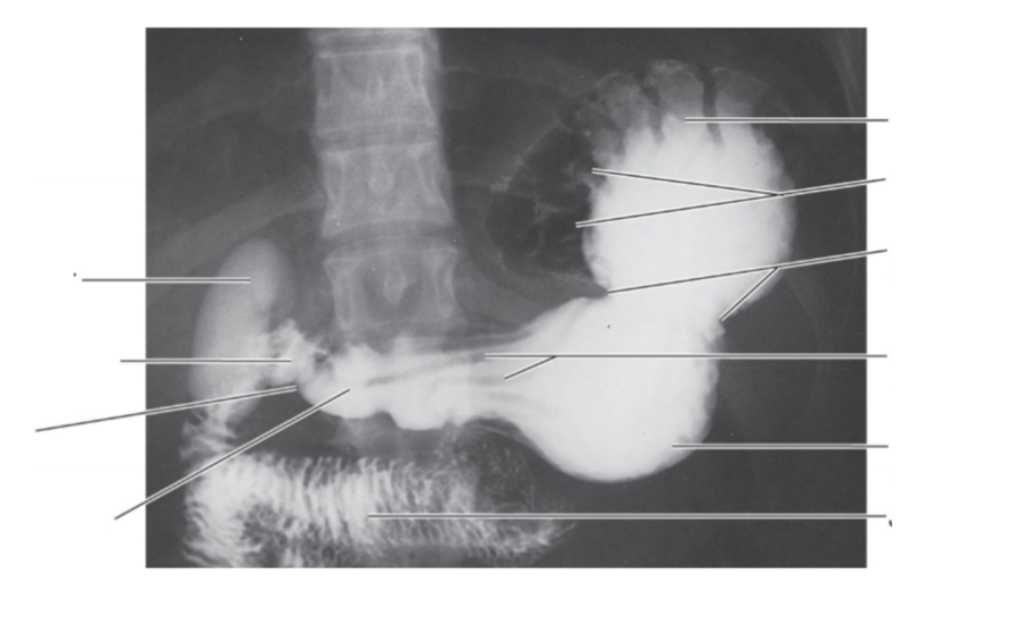

Please label

Function of rugae

Increased surface area of flexibility

When you have a gastric ulcer, what happens to the rugae?

Instead of travelling longitudinally, it goes towards the direction of the ulcer

Function of rugae?

Allows stomach to expand